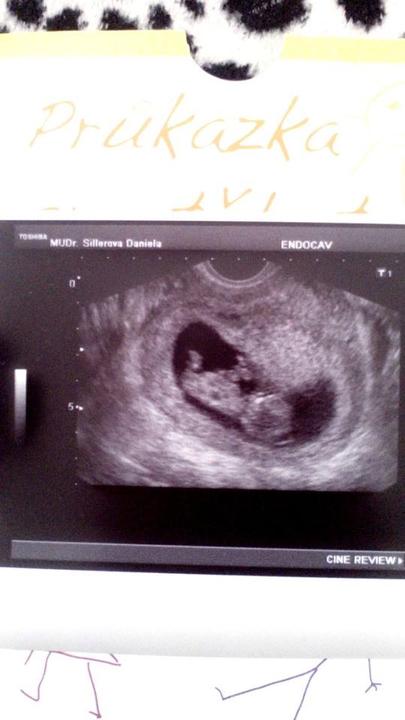

Tak holky kontrola dopadla v pořádku jsem v 11 týdnu akorát jsem zhubla ale snažím se co nejlepe jist ale miláček krásně roste jsem na něj hrdá :3